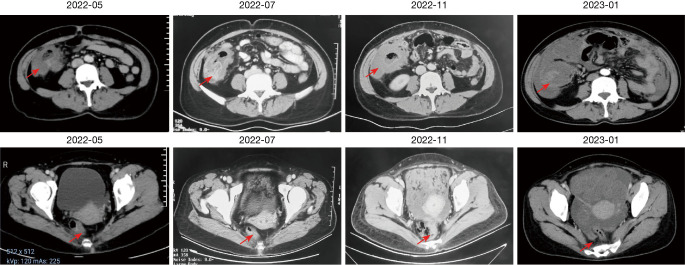

Case description: The patient with double primary CRC, both of which were identified as MSI-H through next generation sequencing (NGS). Following a regimen of immunotherapy-based combination therapy, the rectal lesion achieved a complete clinical response (cCR), while the colon lesion displayed continued progression, indicating primary resistance to treatment.

Conclusions: Specific histological subtypes of CRC, such as mucinous adenocarcinoma, might adversely affect the efficacy of immunotherapy, resulting in primary treatment resistance. Consequently, in the case of this particular cancer subtype, local surgical resection may be a more appropriate treatment strategy.